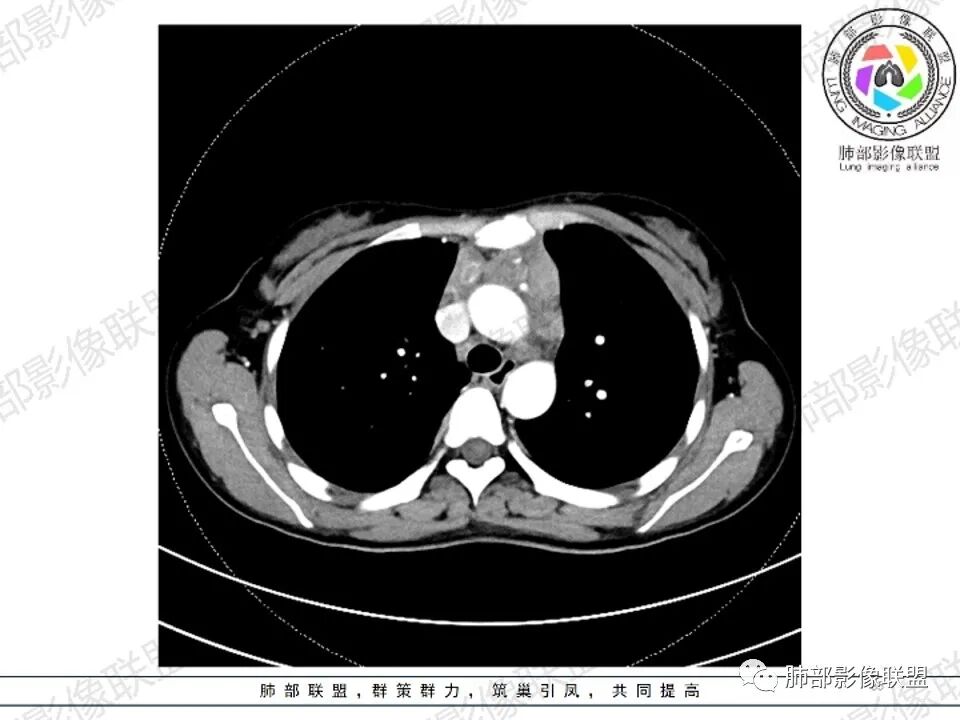

2.影像显示前纵隔不规则块状影,依势贴附心脏大血管旁,密度不均,边界不甚清楚,有结节融合感。

3.病灶轻度不均匀强化,可见血管穿行,散在液性低密度区。

双肺门未见肿大淋巴结。

4.双侧腋窝区见增大淋巴结,边界清楚。

1.年轻女性,前纵隔不规则块状影,密度不均,边界不甚清楚,有结节融合感,轻度不均匀强化,可见血管穿行,最常见最符合的无疑是淋巴瘤!